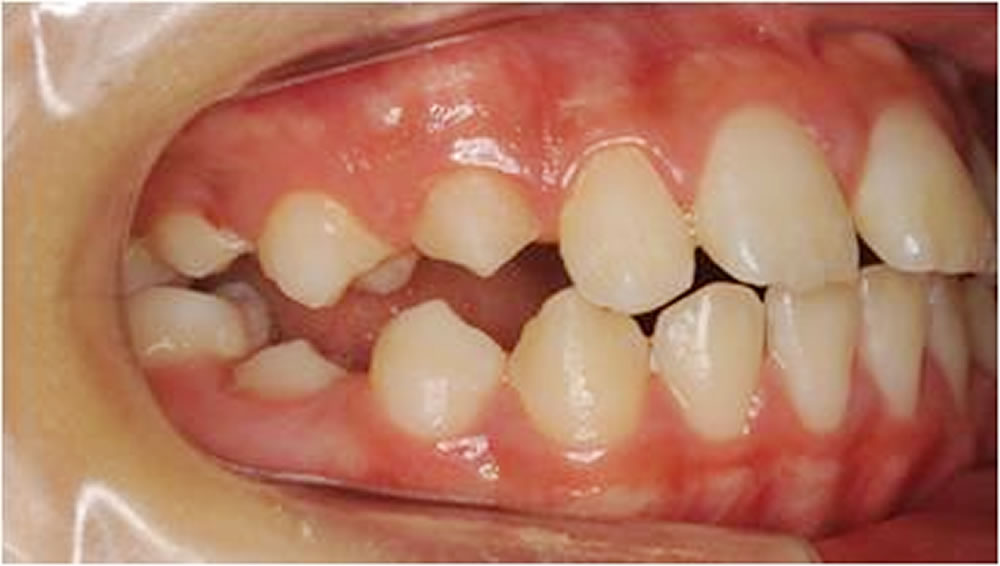

BiVi歯科・矯正歯科で実施した小児矯正の治療例をご紹介

▼当院で実際に行った小児矯正治療の症例をご紹介します。